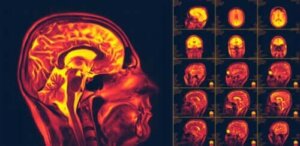

Serebral plastisite olarak da bilinen beyinde nöroplastisite, son dönemlerde insan vücuduyla ilgili en önemli keşiflerden biridir. Beyinde nöroplastisite, beynin yeni davranış ya da deneyimlere uyum sağlayabilmesi anlamına gelmektedir.

Fakat bilim insanları beynimizdeki nöronların sürekli olarak yenilendiğini keşfettiler. Hatta bunun yalnızca anatomik olarak gerçekleşmediğini, aynı zamanda yeni bağlantıların da kurulduğunu bildirdiler. Bu kavrama “nöroplastisite” deniyor. Basit bir şeymiş gibi görünse de esasında olan şey, beynin bazı hasar ya da rahatsızlıklar sonrası kendini iyileştirme yetisi olması.

Bilim insanları bu durumu 1960’lara dek fark edemediler. Felç geçiren bazı yetişkinlerin incelenmesiyle, kaza sonrası iyileşme görülebileceğinin farkına vardılar. Nöroplastisitenin varlığını göstermek adına farklı görüntüleme ve uyarı testleri uyguladılar. Bilim insanları hâlâ bu fenomenin çeşitli özellikleri üzerine araştırmalarını sürdürmektedirler.